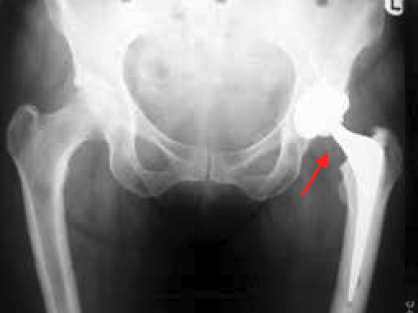

Hip Arthritis is a common condition that occurs when the cartilage which overlies the femur bone or lines the acetabulum bone wears out and exposes ‘bone on bone’ articulation. It is a progressive disorder, meaning it gradually worsens over time.

Osteoarthritis is the most common form, characterised by the breakdown of the joint’s cartilage. The next common form is rheumatoid arthritis, which is a chronic inflammatory disease of the joint and soft tissues.

Less common forms are broadly categorised as ‘inflammatory arthritis’ including such conditions as ankylosing spondylitis, systemic lupus erythematosus (SLE), gout and juvenile arthritis.